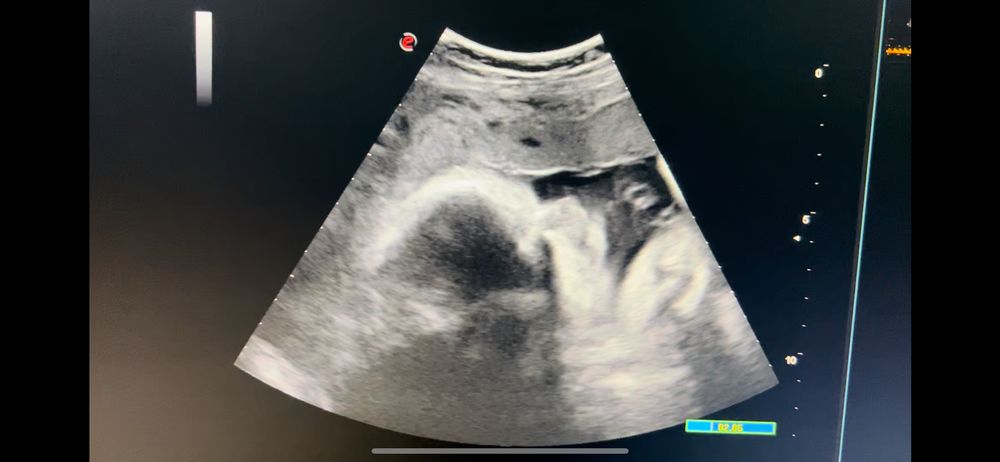

УЗИ, КТГ, доплерВсем привет!😊 Сегодня была в ЖК, сдала анализы (был низкий гемоглобин+ферритин), прошла по УЗИ 3 скрининг, видела свою ягодку❤️.

Потом пошла к своему Г. В общем, по УЗИ, малышка моя весит на неделю меньше - 1580 г. ИАЖ - 10-11 см. Тенденция к маловодию. В связи с чем, назначили повторное УЗИ через 2 недели + КТГ (уже пора по сроку). Плацента немного поднялась (на 2 скрининге была 28 мм) - 4 см. Предлежание головное, но я это и знала. Ощущаю, где попа, голова и ножки)) икает внизу прям. А дубасит ножками вверх/в бок)) Плацента по передней стенке+сбоку. По допплеру все хорошо.

Фотопортрет особо не получился. Малышка спала)